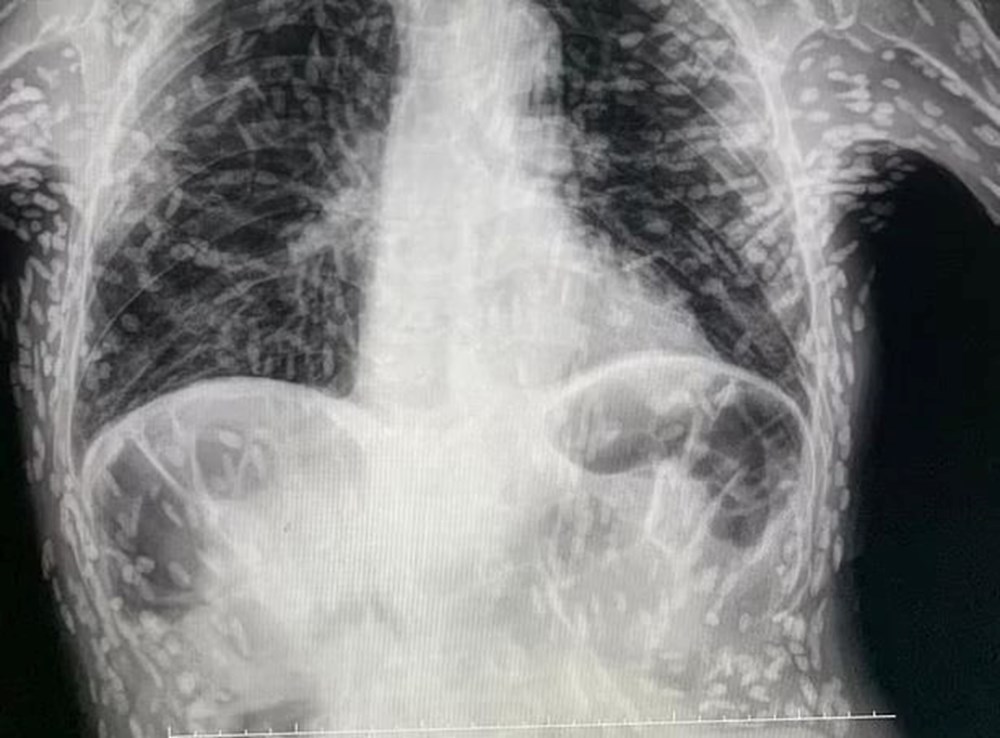

Brezilyalı doktorlar, kendilerini şaşırtan bir vakanın röntgen görüntülerini paylaştı. İyileşmeyen öksürük ve baş ağrısı şikayeti olan hastanın uzun bir zamandır tenyalar tarafından tarafından organlarının delik deşik edildiği ortaya çıktı. Bilim insanları, parazit hastalıkların ölümcül olabileceğini belirterek, gıda hijyenine dikkat edilmesini istedi.

Bir doktorun Twitter'da paylaştığı röntgen, her biri bir parazitin yerleşmiş kalıntılarını temsil eden yüzlerce parlak lekeyi gösterdi.

Sistiserkoz olarak adlandırılan durum, normalde bağırsaklarda yaşayan bir tenya türünün larvalarının kas veya beyin gibi dokulara girmesiyle ortaya çıkıyor. İnsanlar, başta et ve yıkanmamış meyve ve sevze olmak üzere kontamine yiyecekleri kazara yutarak bu tenyalar ile enfekte oluyor. Larvalar, deriden hissedilebilen kistler şeklinde sert yumrular oluşturuyor.

Bununla birlikte, tenyalar hızla öldüğü için durum genellikle zararsız olarak kabul ediliyor. Ancak ölü tenyalar geride bıraktığı kistler ölüme varabilen sağlık sorunlarına neden olabiliyor. Kistler akciğerlerinize yapıştığında ise öksürük ve göğüs ağrısı oluşuyor.

Görüntüyü paylaşan Brezilya'daki Botucatu'daki Hospital das Clínicas'tan Dr. Vitor Borin de Souza, hastanın öksürük şikayetiyle geldiğini ve durumun MRI ile rontgen taramalarında anlaşıldığını söyledi.